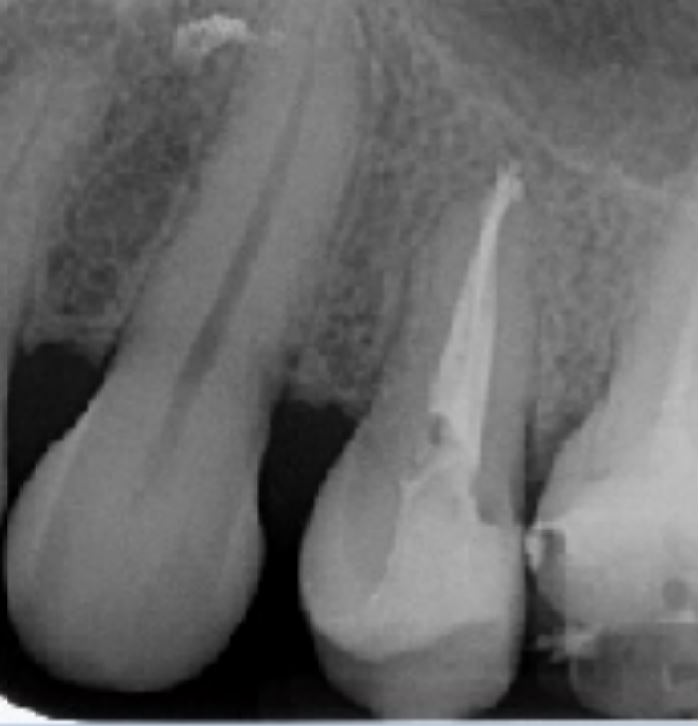

Caso clinico n. 1

Dr. Hetzel Rémy - Bourgoin Jallieu

"Trattamento di premolare con radice corta"

Anamnesi

- Dente aperto in pronto soccorso - ambiente ospedaliero

- Lima manuale K20 passata molto facilmente oltre l'apice

- Sospetto di diametro apicale non rispettato

- Prima radiografia con lima manuale K25

Radiografia intraoperatoria

- Passaggio di serie sequenziali di lime manuali

- Lunghezza di lavoro determinata con lima K20

- Lunghezza di lavoro fissata a 17,5 mm

- Lima apicale maestra di 30/100

- Sagomatura con la sequenza Fanta ROTARY fino alla lima 30/04%

Radiografia postoperatoria

- Otturazione con guttaperca e cemento all'ossido di zinco-eugenolo

- Termocompattazione

- Restauro in composito a 2 superfici occluso-distale